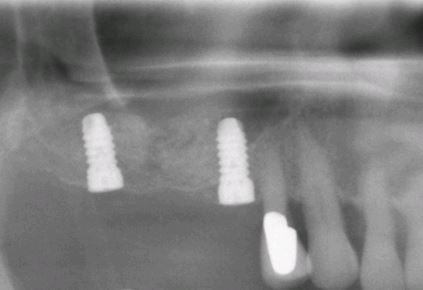

zahnimplantat backenzahn

Wenn mehrere Zähne, auch nur auf einer Seite des Gebisses endständig fehlen, kann keine festsitzende Brücke mehr herkömmlich hergestellt werden . Hier hat der Patient nur die Möglichkeit eine sogenannte Teilprothese zu tragen, die sich auf der Oberfläche der Kiefer abstützt. Diese hat also eine recht grosse Oberfläche und muss zudem für den Patienten herausnehmbar sein um sie von allen Seiten reinigen zu können. Möchte der Patient eine solche Konstruktion nicht tragen, so kann man nur durch das Einbringen von Zahnimplantaten wieder festsitzende Zähne in diesem Kiefergebiet bekommen. Wenn nach Jahren des fortschreitenden Zahnverlustes nur noch wenige einzelne Zähne vorhanden sind, so wird es sehr häufig für den Patienten sehr unangenehm, den herausnehmbaren Zahnersatz in einer halbwegs zufriedenstellenden Weise zu tragen. Es stellen sich weitere Probleme mit dem Essen und der Aussprache ein. Ein einheitliches Erscheinungsbild der eigenen natürlichen Zähne und dem künstlichen Zahnersatz ist ebenso kaum herzustellen. Hier können ebenfalls Zahnimplantate Abhilfe schaffen, indem sie zusätzliche Haltepunkte darstellen, an denen ein kompletter Zahnersatz aufgebaut werden kann.